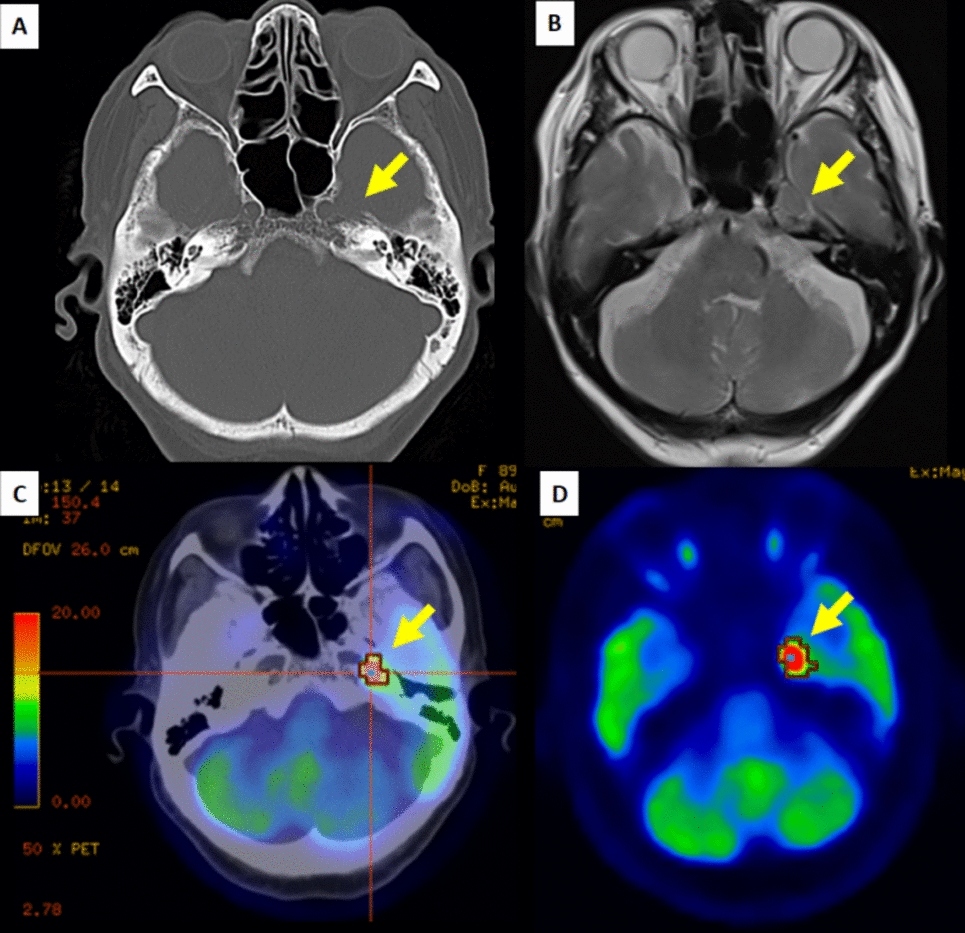

Stereotactic body radiation therapy (SBRT) is the standard treatment for patients who are medically inoperable or who refuse surgery with stage I non-small cell lung cancer (NSCLC). While acute lymphopenia following SBRT is documented, the long-term effects on the immune system and infectious disease remain unclear. In this report, we present two cases of chronic progressive pulmonary aspergillosis (CPPA) occurring within the irradiated field following SBRT for inoperable stage I NSCLC. Case 1 was a man in his 70 s with a history of smoking and a previous pulmonary resection and SBRT for metachronous primary lung cancer. He received SBRT for T1aN0M0 NSCLC in the right lower lobe as his third primary lung cancer. After 20 months, the patient developed a cough and sputum, and a computed tomography (CT) scan revealed a cavity shadow in the irradiated field, which led to the diagnosis of CPPA. Intravenous voriconazole was immediately started, and after 3 week’s administration, the symptoms improved, and the cavity disappeared. After 34 months, the patient died with no recurrence of CPPA and lung cancer. Case 2 was a man in his 80 s with a history of smoking and previous pulmonary resection for lung cancer. He received SBRT for T1cN0M0 NSCLC in the right lower lobe as his second primary lung cancer. After 19 months, the patient developed a fever, and a CT scan revealed a cavity shadow in the irradiated field, which led to the diagnosis of CPPA. Oral itraconazole was administered, followed by diarrhea and anorexia. After 22 days, the patient died. During the follow-up period, there was no recurrence of lung cancer. Risk factors for CPPA include a history of smoking and lung resection, common among candidates for pulmonary SBRT. When a cavity shadow develops following SBRT, differentiating consolidation as radiation pneumonitis, local recurrence, or infection can be challenging. When a cavity is identified on a follow-up CT scan after SBRT, it is crucial to include CPPA in the differential diagnosis.